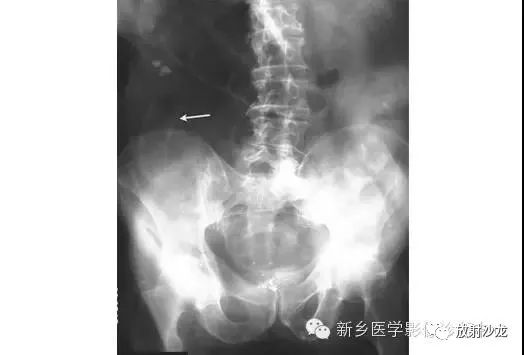

上图腹部平片检查是一6岁男孩,出现呕吐和急性右髂窝疼痛进行的。两个关键的发现在哪里?(提示:通过放射科医生所提供的箭头可以缩小关注点。)

右髂窝多个扩张的小肠襻出现小的钙化结节。小肠袢可与大肠区分开来,因为小肠的环状襞延伸至整个肠壁,而结肠袋只是部分延伸存在。在右下腹(箭头)的钙化结节高度提示阑尾粘连。这个病人开腹手术发现阑尾粘连致小肠梗阻。